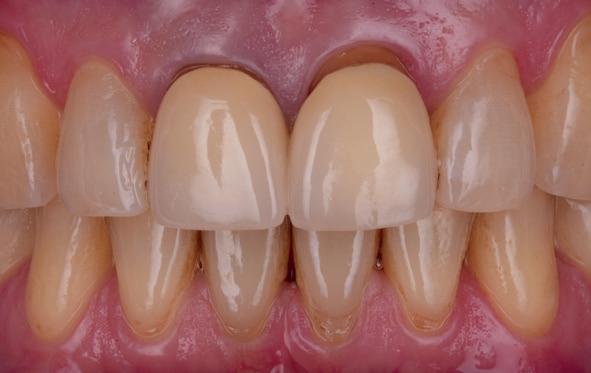

tinaal geslepen te worden als er geen 1,5 mm ruimte voor de vleugels behaald kan worden. De ruimte was op de dunste plekken 1 mm, dus een kleine preparatie in de 12 en 22 palatinaal was nodig. Omdat de kaak volledig afgevlakt was en dun was geworden, kunnen de dummies van de etsbrug enkel op de kaak “gelegd worden”, maar daarbij zijn er geen papillen en staat de cervicale rand van de dummies net voor de kaak. Een esthetisch resultaat kan daarmee niet behaald worden. Daarom is een aanvulling van de zachte weefsels in de breedte nodig, als het creëren van een emergence profile, waarbij het oogst alsof de gebitselementen uit het weefsel vertrekken.

14. Direct postoperatief plaatsen

van de essix met 2 dummy tanden

16. Creëren van een duidelijke indeuking in de mucosa voor emergence profile